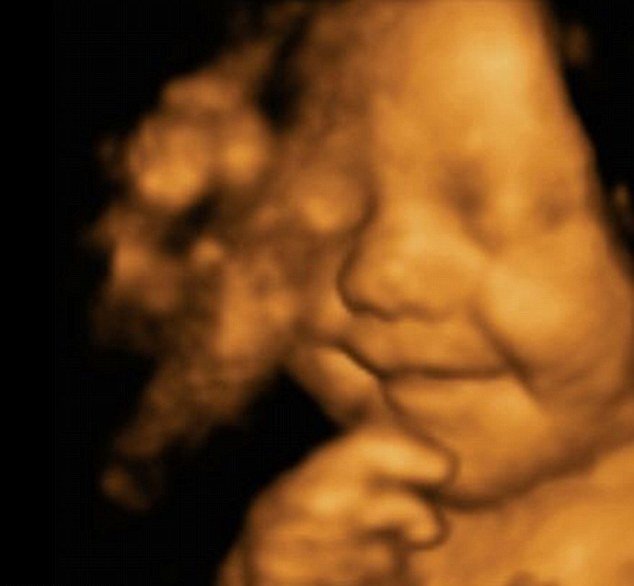

Este bebé empezó a sonreír antes de nacer y no ha dejado de hacerlo… ¡Hermoso!